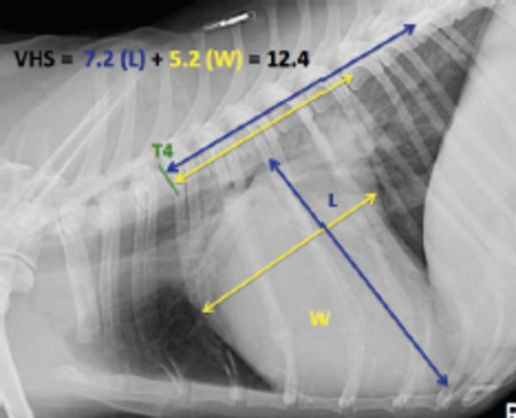

Radyografi

Kalp hastalıklarında kalbin bulunduğu göğüs boşluğunun röntgen ile değerlendirilmesi, kalbin boyutları ve çevre dokuların durumları hakkında bilgi edinmek amacıyla radyografiden faydalanıyoruz. Herhangi bir yatıştırıcı ya da anestesiye ihtiyaç duyulmadan çok düşük dozda X ışınları ile dijital radyografiler ile muayenemizi tamamlıyor; tüm dünyada kabul görmüş değerlendirme skalaları ile ölçümleri yapıyoruz